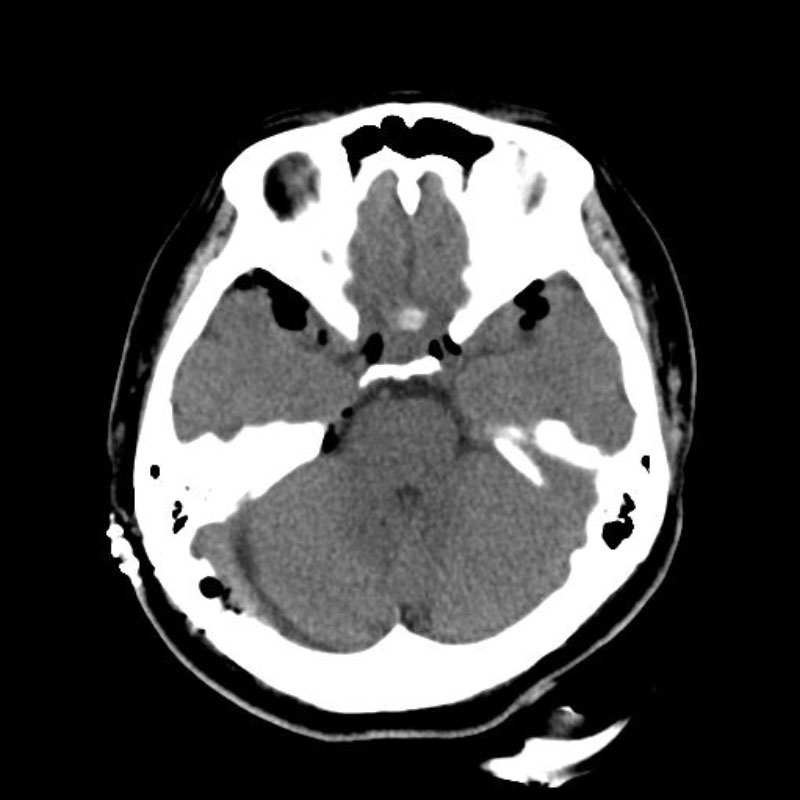

手術後

(CT)